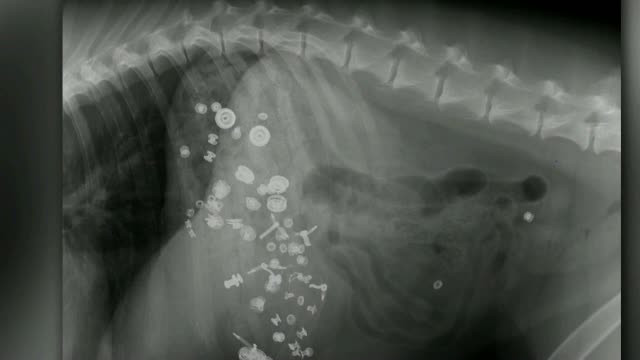

Un barbat a inghitit sute de monede, cuie si alte metale pentru ca era depresiv. Medicii au fost socati cand l-au examinat

Joi 23 Aprilie 2015

Un barbat din India a uimit medicii care i-au scos din stomac sute de monede si cuie, ...